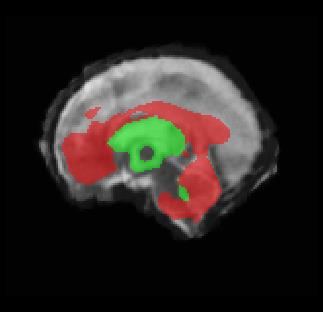

Limiting failures of machine learning systems is of paramount importance for safety-critical applications. In order to improve the robustness of machine learning systems, Distributionally Robust Optimization (DRO) has been proposed as a generalization of Empirical Risk Minimization (ERM). However, its use in deep learning has been severely restricted due to the relative inefficiency of the optimizers available for DRO in comparison to the wide-spread variants of Stochastic Gradient Descent (SGD) optimizers for ERM. We propose SGD with hardness weighted sampling, a principled and efficient optimization method for DRO in machine learning that is particularly suited in the context of deep learning. Similar to a hard example mining strategy in practice, the proposed algorithm is straightforward to implement and computationally as efficient as SGD-based optimizers used for deep learning, requiring minimal overhead computation. In contrast to typical ad hoc hard mining approaches, we prove the convergence of our DRO algorithm for over-parameterized deep learning networks with ReLU activation and a finite number of layers and parameters. Our experiments on fetal brain 3D MRI segmentation and brain tumor segmentation in MRI demonstrate the feasibility and the usefulness of our approach. Using our hardness weighted sampling for training a state-of-the-art deep learning pipeline leads to improved robustness to anatomical variabilities in automatic fetal brain 3D MRI segmentation using deep learning and to improved robustness to the image protocol variations in brain tumor segmentation. Our code is available at https://github.com/LucasFidon/HardnessWeightedSampler.